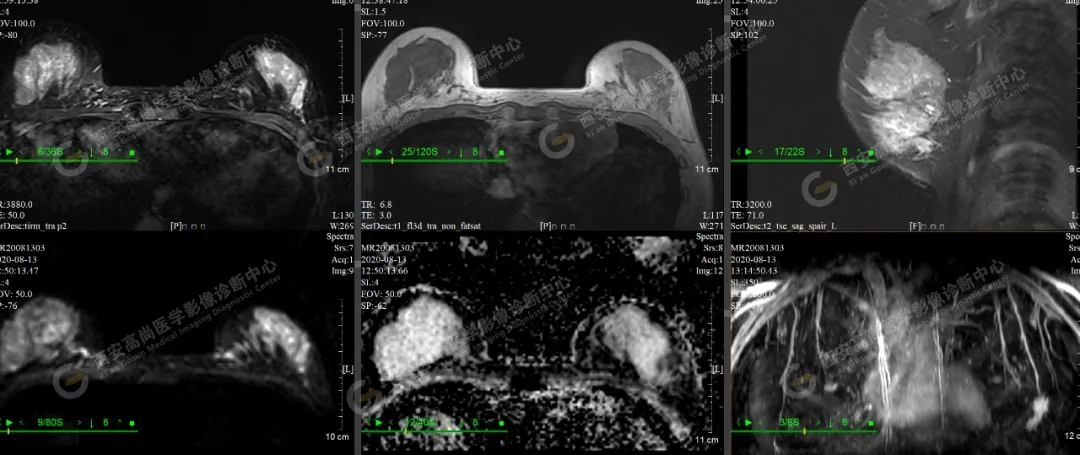

【病例一】女性,30歲,左側(cè)乳腺外下象限乳腺Ca(BI-RADS IV-V級)